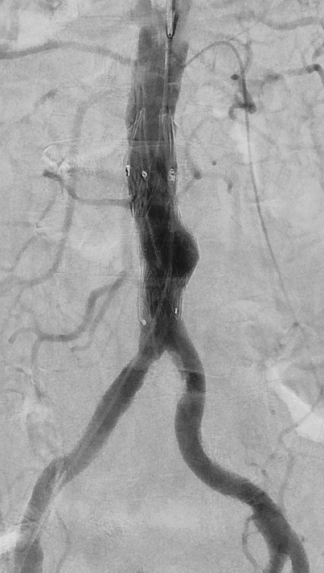

This was treated by interventional radiology using pinhole techniques. A small access was placed in the right groin artery (right CFA) and repair was done endovascularly using a Medtronic Renu cuff. The device was placed percutaneously and the access site closed using Proglide closure device by Abbott.

Whole procedure done under local anaesthetic and completed in 20 minutes. Patient was asymptomatic following the procedure and discharged the following day.